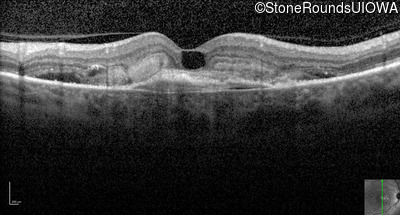

Visit at age: 58 years (Visit 3)

Optical Coherence Tomography - Right - 20/80 +1

Exemplar / OCT Stack